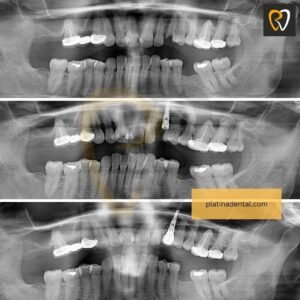

2️⃣ Multiple Teeth Implants

When several teeth are missing, implants can support multiple crowns or bridges without affecting neighboring teeth.